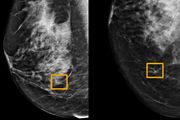

Google har utviklet kunstig intelligens som gjenkjenner brystkreft bedre enn radiologer